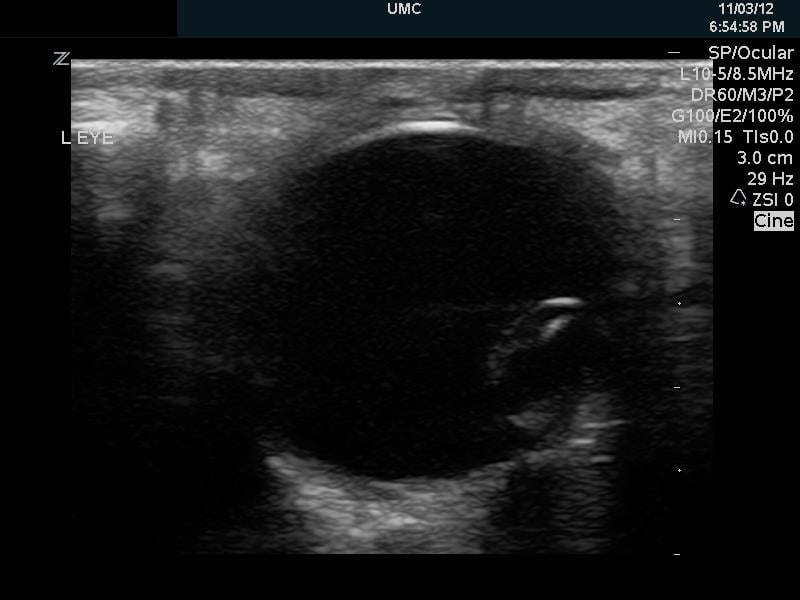

Retinal Detachment (RD)

- RDs may be difficult to diagnose on physical examination, especially if the RD is small.

- Ocular ultrasound to diagnose RD has sensitivities of 0.97 to 1.00 and specificities of 0.83 to 1.00.7

- Attachment sites of the retina are: ora serrata in the anterior globe and the optic nerve posteriorly.

- Occasionally, retinal tears are accompanied by vitreous hemorrhages, retinal hemorrhages, and/or PVDs.

- Retinal hemorrhages will be located below the retina.

- A retinal detachment will be seen as a hyperechoic undulating membrane in the posterior globe, extending to the lateral globe.

- Complete RDs may appear as a V shape and will be tethered to the optic nerve.

- RD is usually seen as a thicker, more linear membrane then the undulating, thinner membrane of PVD.

- The macula is temporal to the optic nerve. It cannot be visualized sonographically though location can be approximated by the location of lens (see Fig. 8). If the RD extends temporally from the base of the optic nerve, it can be assumed that it has come off of the macula (“mac off retinal detachment”).

- RD with the retina still over the macula is an ocular emergency warranting an emergent consultation to ophthalmology in order to take measures to prevent the retina from coming off of the macula.

- RD with the retina off the macula requires an urgent follow-up with ophthalmology.